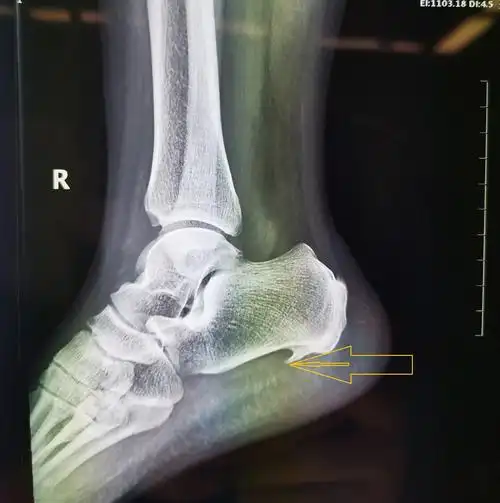

请骨科战友帮忙看一下左踝关节x线片 [病例帖]

左侧踝关节外伤x光

多见于老年患者,当有脚后跟痛时,经过拍摄x光片,可以发现跟骨结节处有